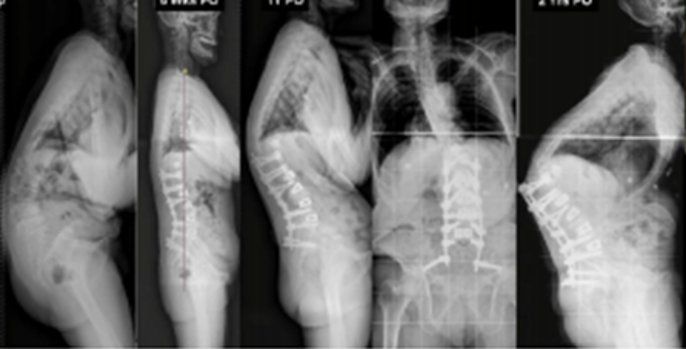

(8)脊柱矫形的程度

1) 矢状面失平衡(High SVA)过度矫正

术前-术后SVA矫正过大(大于5cm)的患者,PJK发生的风险增高

矫形术后矢状面失平衡可增加固定融合近端和远端交界区的应力,增加PJK风险

图16 矢状面失平衡过度矫正

SVA随着年龄增加,理想SVA矫正应综合考虑患者病情采用个性化矫形方案。

2)腰椎前凸(LL)过度矫正

图17 据文献报道,腰椎前凸(LL)过度矫正和SVA基线位置不当,均为增加PJK发生的风险因素